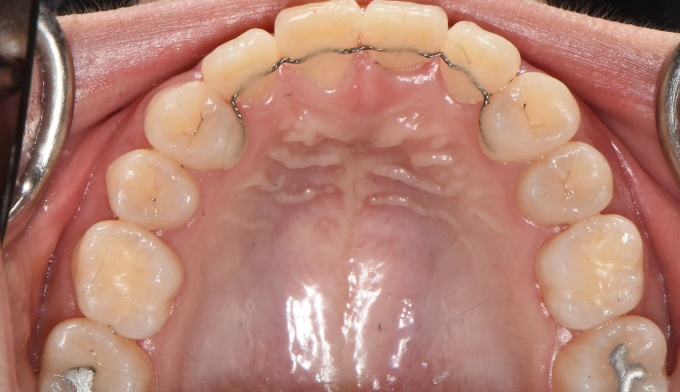

Before

위쪽 송곳니가 엑스레이상에서도 거의 코 옆쪽으로 매복되어 있는 케이스입니다.

매복치에 접근하는것이 무리라고 판단되어 유치만 발치하고 진행하기로 하였습니다.